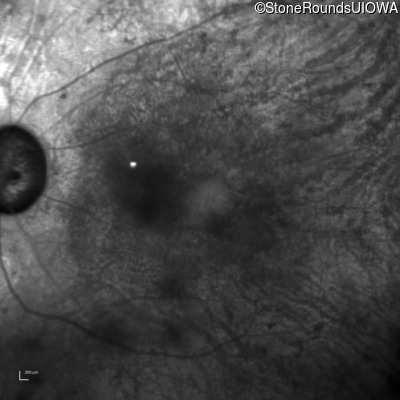

Age at visit: 62 years

OD OS

This 62 year old man had poor night vision as a teenager and developed difficulty with his peripheral vision in his early forties. His parents both grew up in the small village in Taiwan.

Diagnosis & molecular findings

Disease Gene Allele 1 variant(s) Allele 2 variant(s) Inheritance mode

AR Retinitis Pigmentosa EYS Cys2139Tyr TGT>TAT Cys2139Tyr TGT>TAT AR